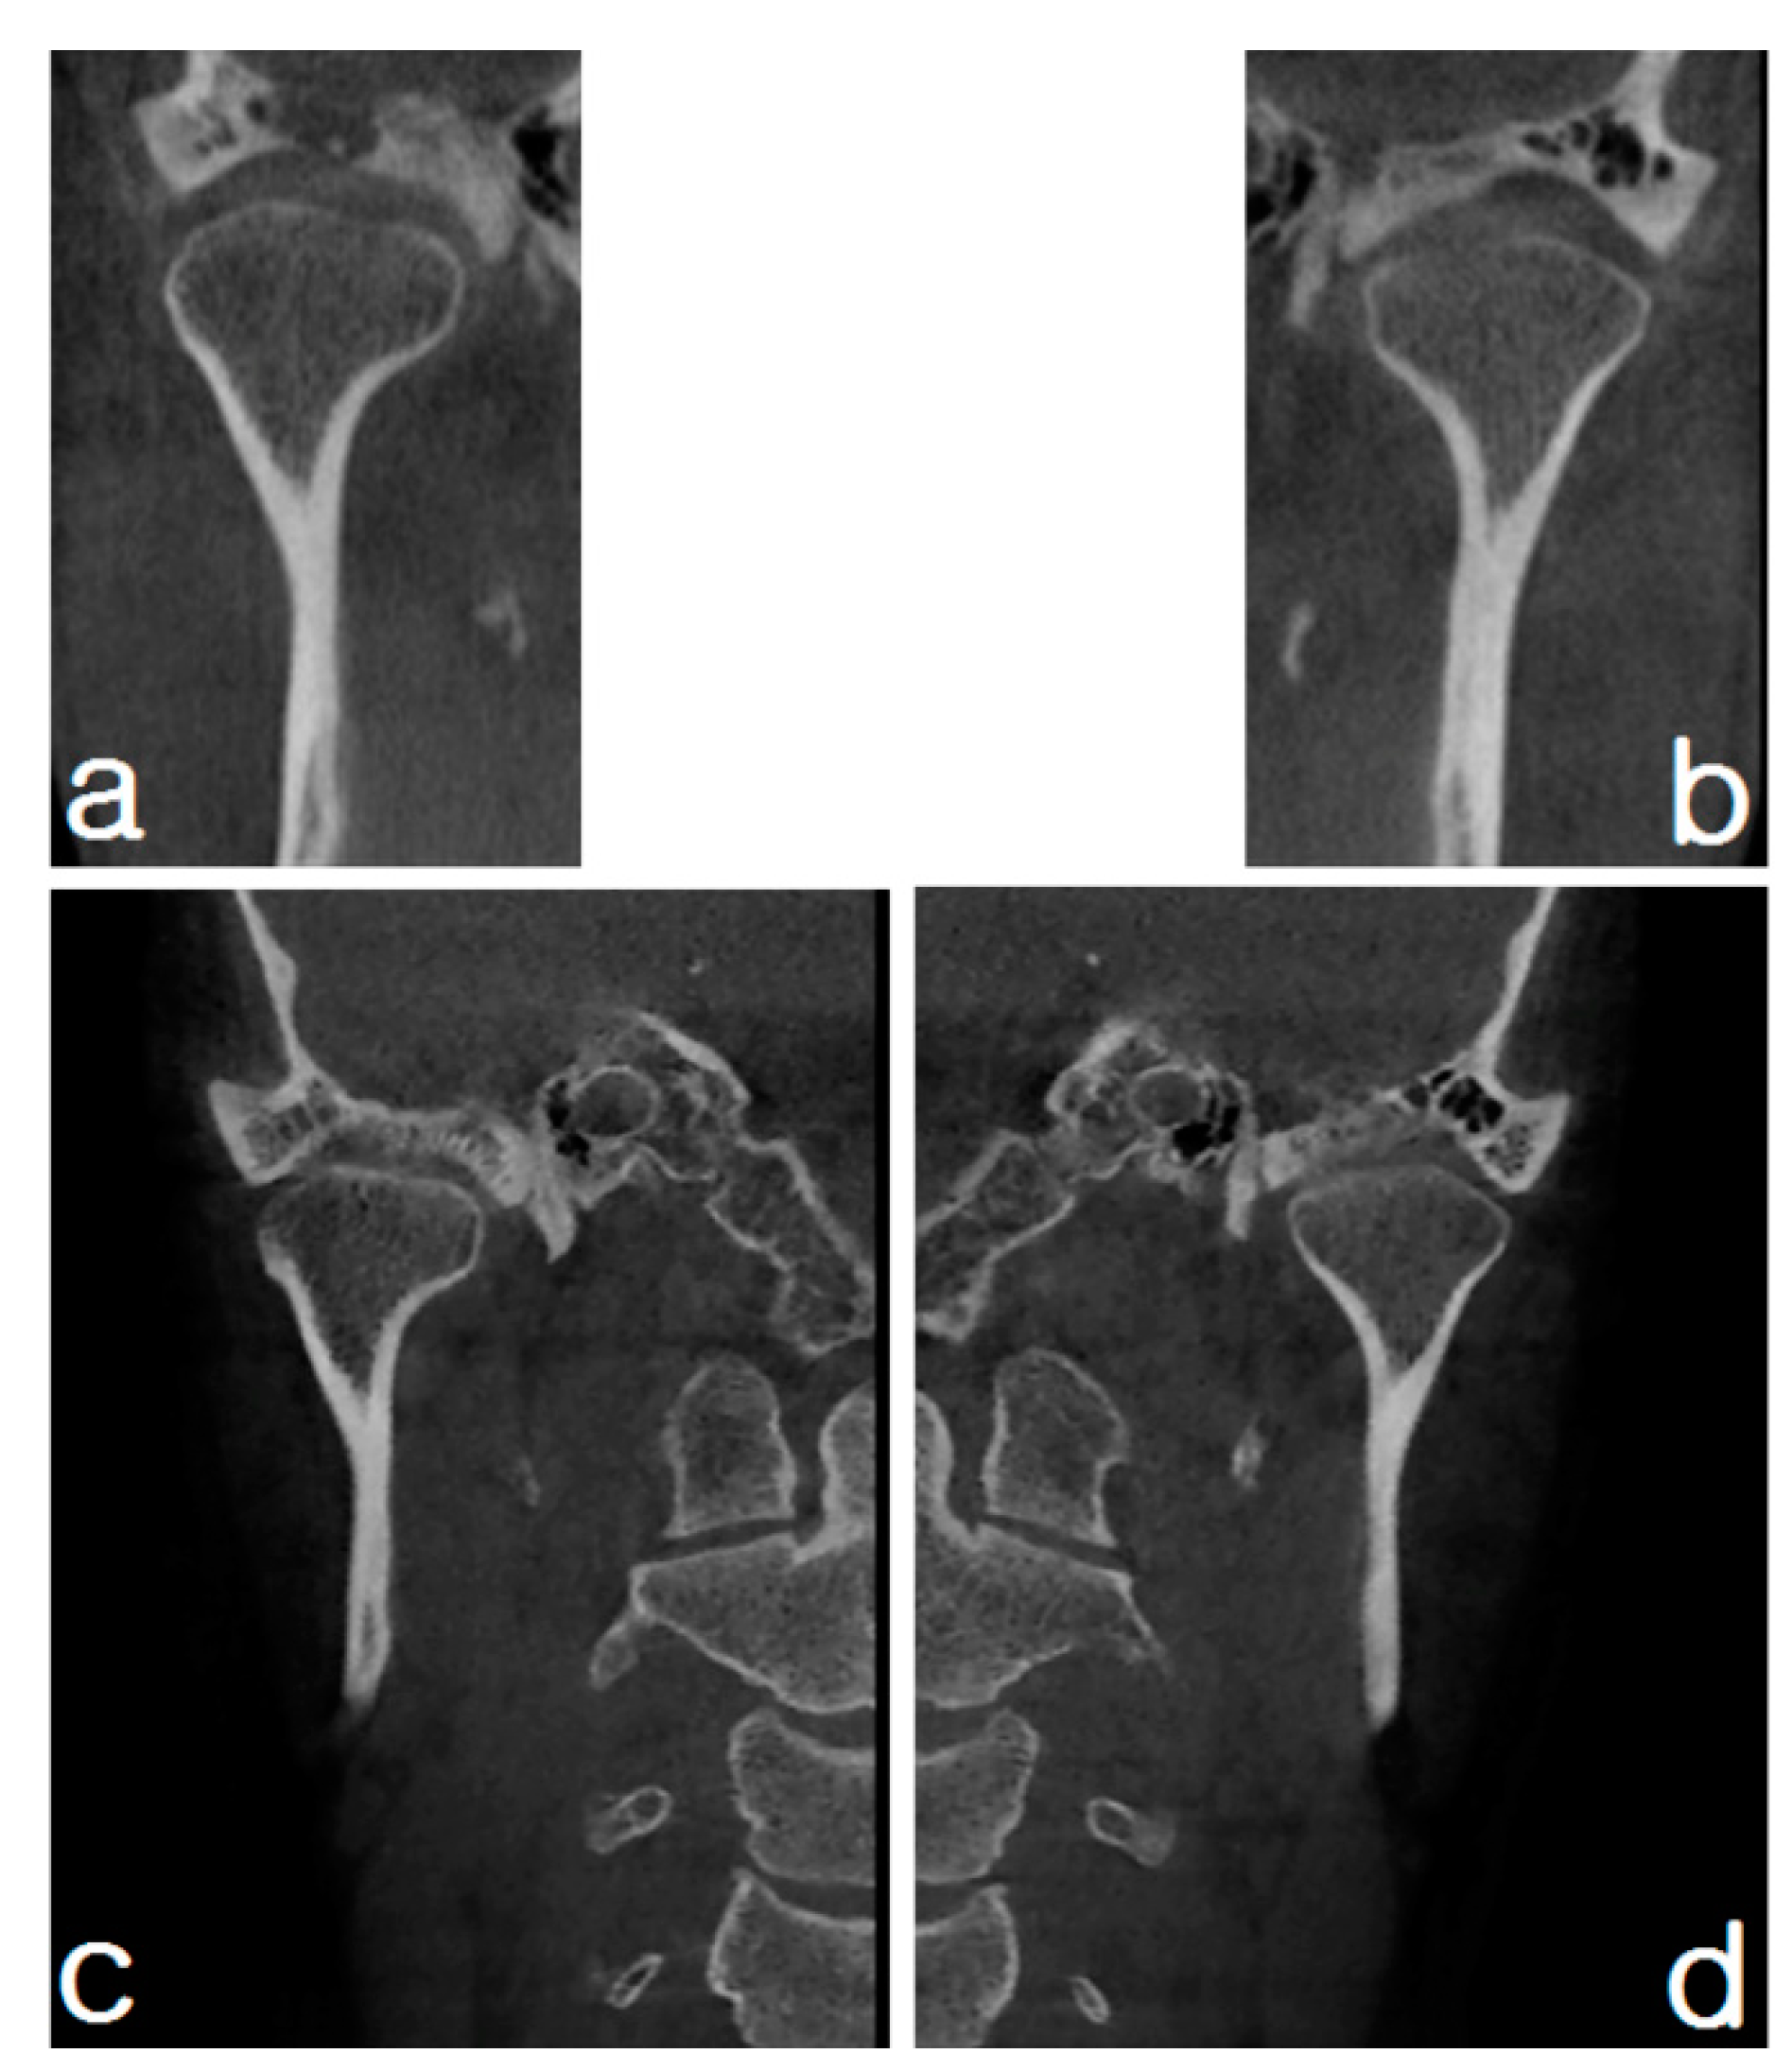

2.1.2. Imaging

2.2.2. Imaging